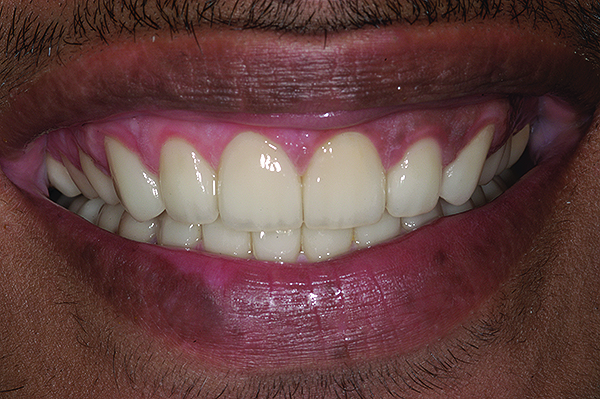

Figure 19. Postoperative frontal smile.

Figure 19

The final restorations depicted restoration of form, function, and beauty, with good harmony of restoration and the periodontium (Figure 19 through Figure 25). MIP was in harmony with CR, and right and left lateral excursion discluded all posteriors with anterior group function. The postoperative orthopantomogram (OPG) (Figure 26) shows the treatment done while maintaining the vitality of anterior teeth.